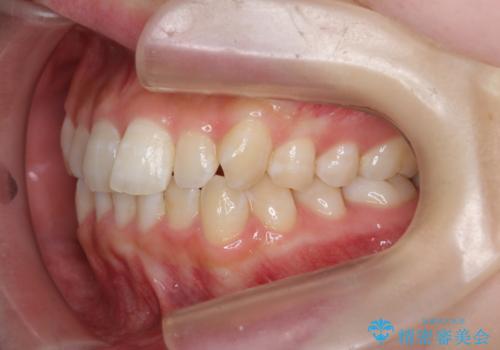

前歯のねじれを治したい マウスピース矯正治療

- 前歯のねじれを改善し、きれいな歯並びにしたい!と矯正治療を希望され来院されました。

マウスピース矯正システム、インビザラインのシミュレーションを用いて最終的な歯の位置をしっかりと確認したのち、きれいな歯並びとなるようマウスピース矯正治療を開始します。

ねじれとともに突き出たように見えていた前歯も見た目が大きく改善し、喜んでいただくことができました。